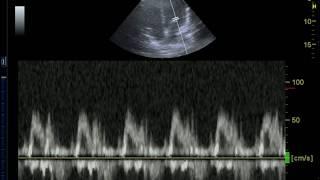

Acquiring the Mitral Inflow View with Pulse Wave Doppler for Diastolic Dysfunction Evaluation

POCUS 101

8K

27,232

5 лет назад